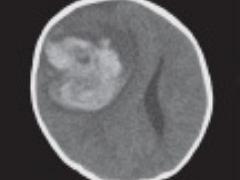

Patiënten met een stollingsstoornis worden niet altijd herkend op de Spoedeisende Hulp, toch is dit van levensbelang. Er zijn verschillende stoornissen, waaronder hemofilie en de ziekte Von Willebrand. Bij hemofilie ontbreekt volledig of gedeeltelijk het stollingseiwit factor 8 (VIII, hemofilie A) of factor 9 (IX, hemofilie B). Afhankelijk van de ernst, kunnen bloedingen optreden in gewrichten, spieren of bloedingen na een medische ingreep of trauma. De ziekte Von Willebrand komt voornamelijk tot uiting via slijmvliesbloedingen of als (na)bloedingen na een medische ingreep, met name na een kiesextractie of tonsillectomie. Deze aandoeningen vragen een specifieke behandeling bij een trauma. Het is van belang dat bij een trauma binnen drie uur stolling wordt toegediend, om inwendige bloedingen te voorkomen, voordat verdere diagnostiek plaatsvindt.